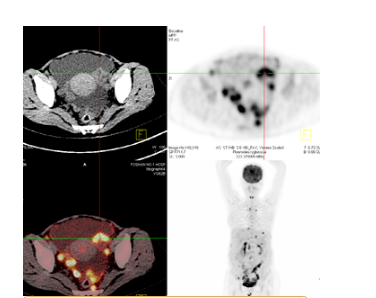

PET-CT:

1.盆腔左侧附件区囊实性恶性病变(卵巢癌?)。

2.腹盆腔广泛腹膜转移,其中盆腔病灶与右侧附件、相邻小肠及直肠分界不清;

3. 腹盆腔大量积液。

4. 腹腔、腹膜后区及盆腔内广泛淋巴结转移。胸骨两旁内乳区、纵隔右膈肌脚旁、双膈上淋巴结肿大,考虑转移。

5.右侧斜裂旁增殖灶;其余纵隔及双肺门淋巴结反应性增生;胆囊结石;双肾结石。